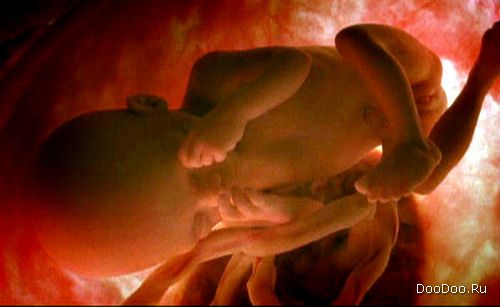

Шестой месяц. Почти полностью сформирован зародыш.

Последние стадии беременности. Его пять чувств уже активны.

7 месяцев. Его мозг и спинной мозг полностью развиты. Мускулы его небольшого сердечка развиты, оно начинает биться немного спонтанно.